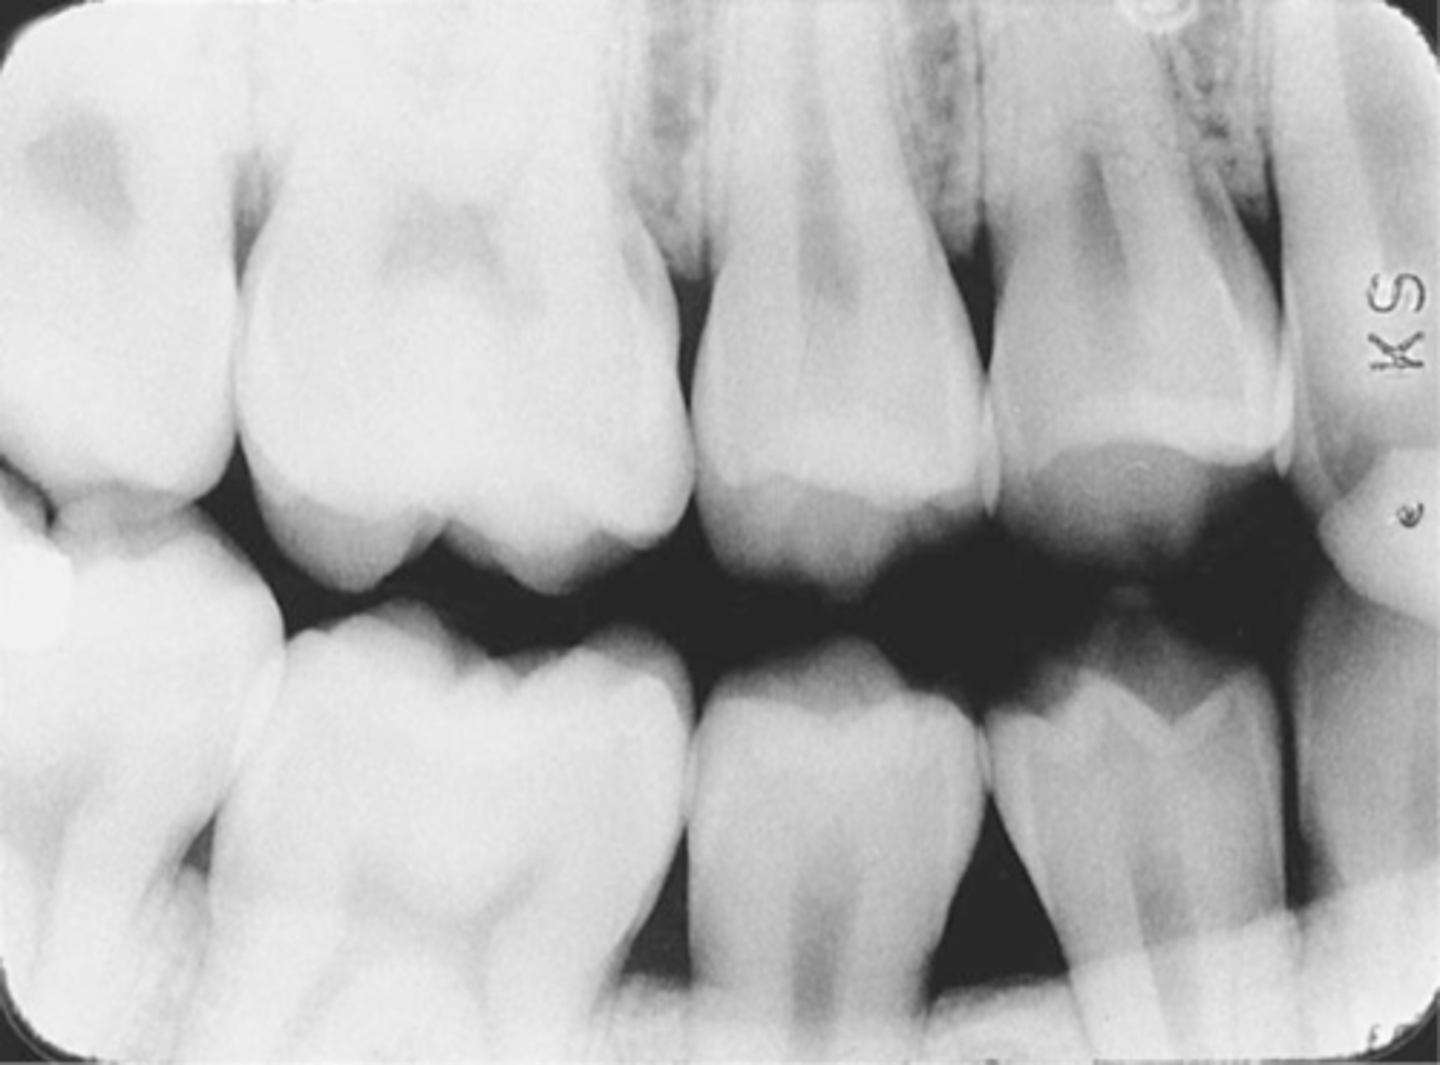

Incorrect Receptor Placement--Premolar Bite-Wing

-Distal surfaces of canines are not visible on the image

-Receptor was positioned too far posteriorly in the mouth; front edge of the receptor was not placed at the midline of the mand. canine.